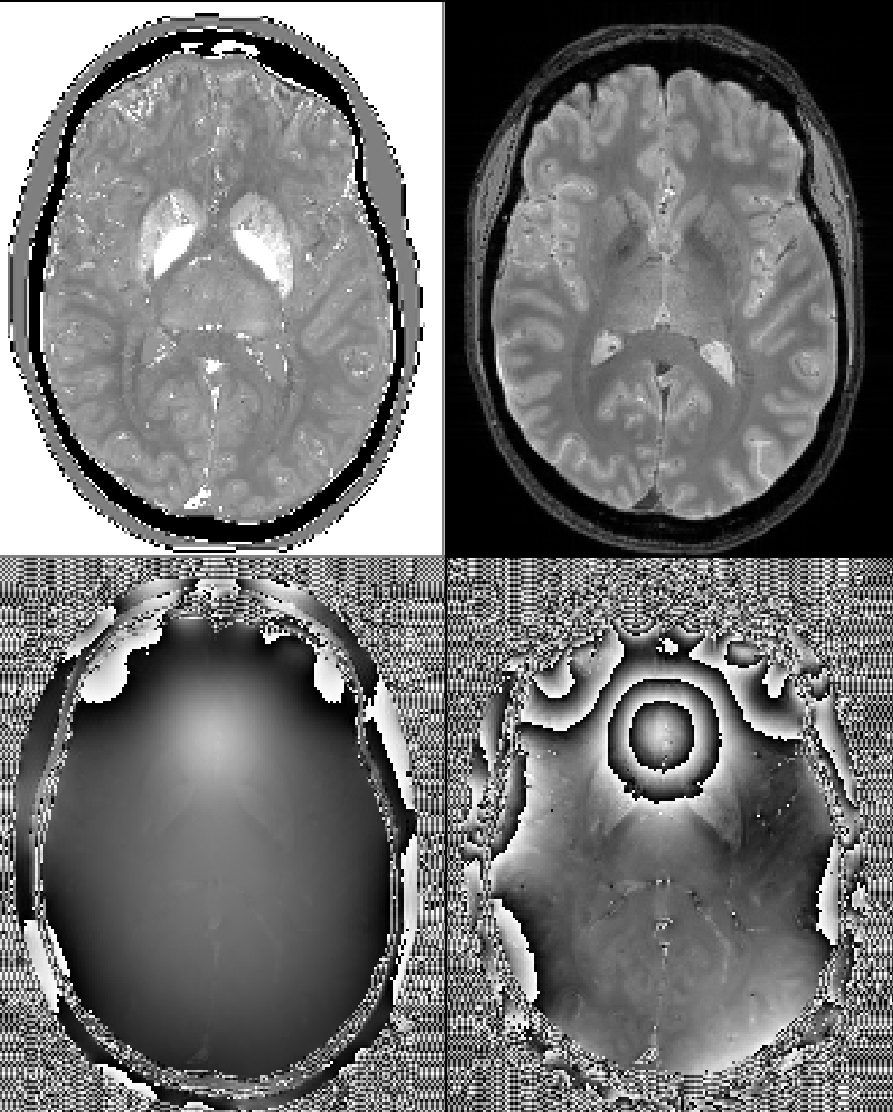

Some repesentative images including the ground truth chi map, first-echo magnitude image, and first and last-echo phase images: